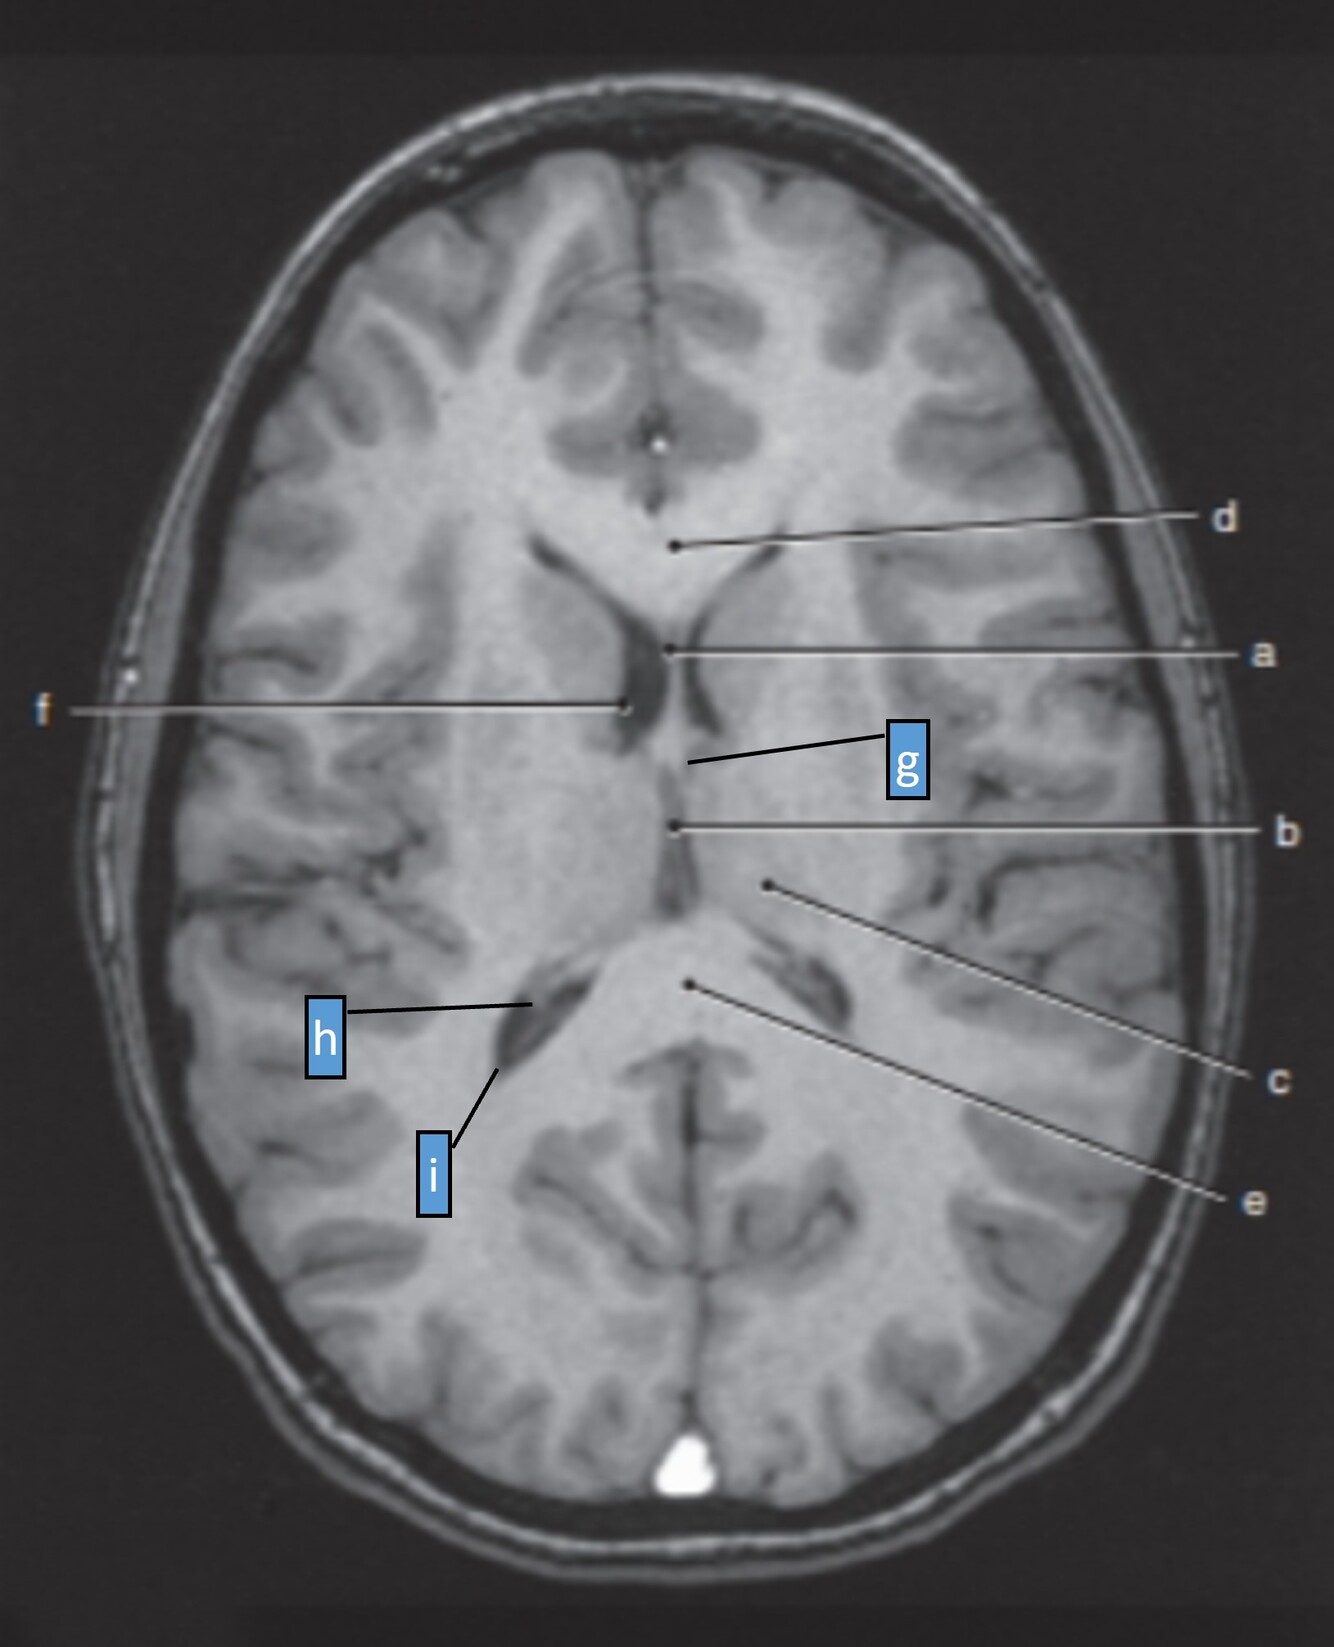

25

Label f-i

f-Rt lateral ventricle g=Lt foramen of Monro (interventricular foramen) h=Choroid plexus (of rt lateral ventricle) i=Posterior horn (rt lateral ventricle